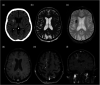

Cavernous malformations are angiographically occult vascular malformations. They are often associated with a developmental venous anomaly through poorly understood mechanisms. We present an unusual case of a gradually enlarging cavernous malformation associated with a developmental venous anomaly with arteriovenous shunting, suggesting venous hypertension or reflux as a potential cause of progressive growth.